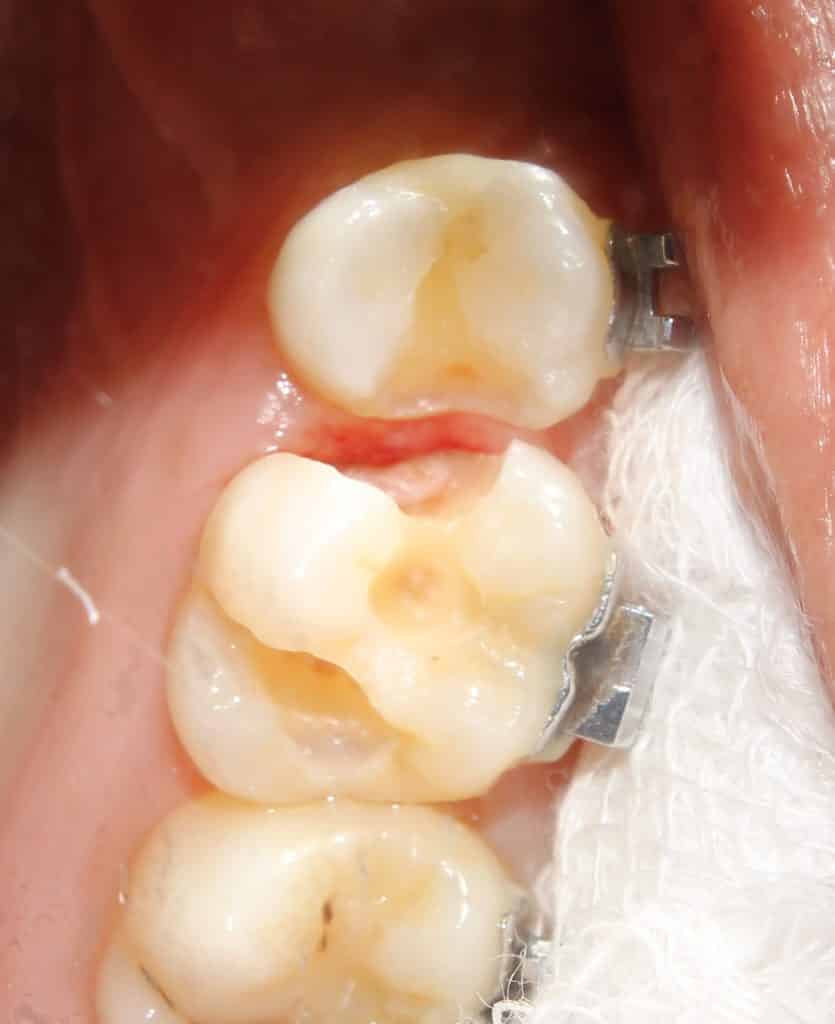

initial entry into 15 showing the proximal caries..

on entry.. the caries on the mesial of the molar is seen..